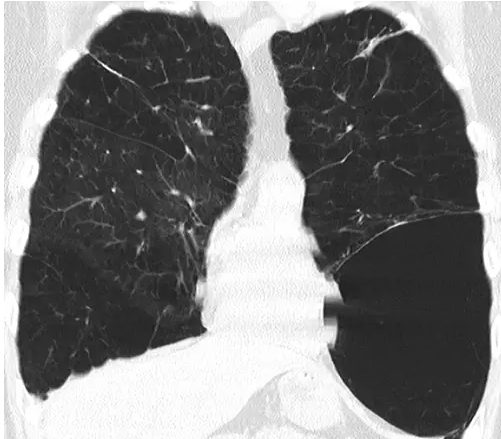

胸片和CT表现

肺大疱表现为圆形的局部透亮影或密度减低区,直径≥1cm,以薄壁为界(图3)。多发肺大疱很常见,并与其他肺气肿的征象(小叶中心气肿或小叶间隔周围肺气肿)相关。

图3